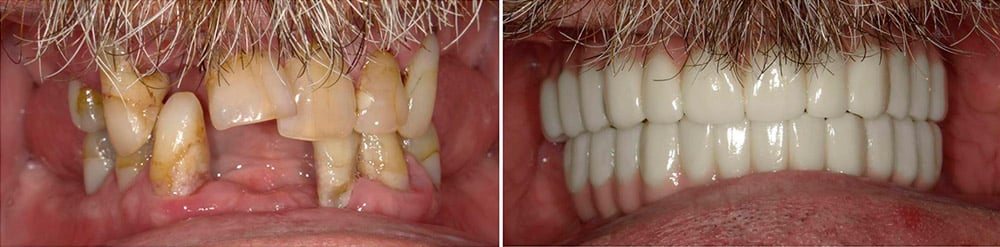

Before & After